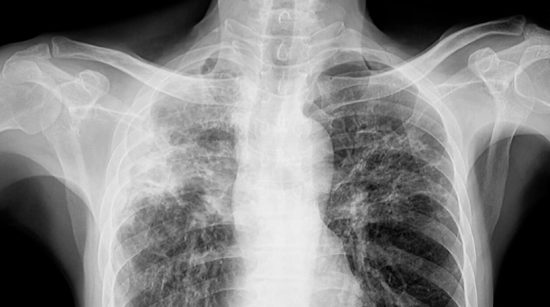

結核病是由結核分枝桿菌引起的傳染病。首次接觸這種微生物後,結核病可能迅速發展,也可能在數年後出現。

結核病的症狀包括持續數週的咳嗽、發燒、極度疲勞、食慾下降、盜汗和體重減輕。據保健部說,結核病需要服用多種藥物,療程數月,大多數患者只要按醫囑服藥就能康復。

然而艾哈邁·汗表示,結核病會在患者身上留下後遺症,例如肺部瘢痕或影響心臟和血管,導致患者在日常活動中呼吸困難。「這些影響可能會持續終生,」他說。